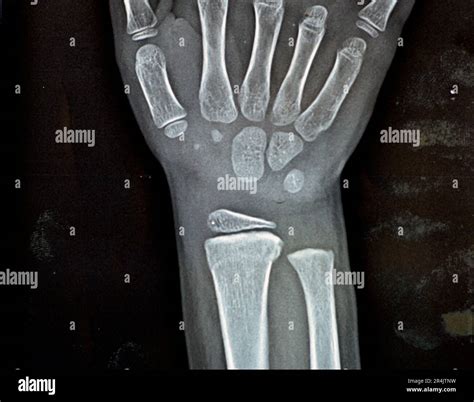

A Normal Wrist Xray is a radiographic image of the wrist that shows the bones, joints, and surrounding soft tissues. It is commonly used to diagnose fractures, dislocations, and other abnormalities in the wrist area. The procedure is non-invasive and relatively quick, making it a preferred method for initial assessments.

Interpreting a Normal Wrist Xray requires a trained eye. Radiologists look for several key features:

• Bone density and structure

• Alignment of the bones

• Presence of fractures or dislocations

• Signs of arthritis or other joint disorders

• Soft tissue abnormalities